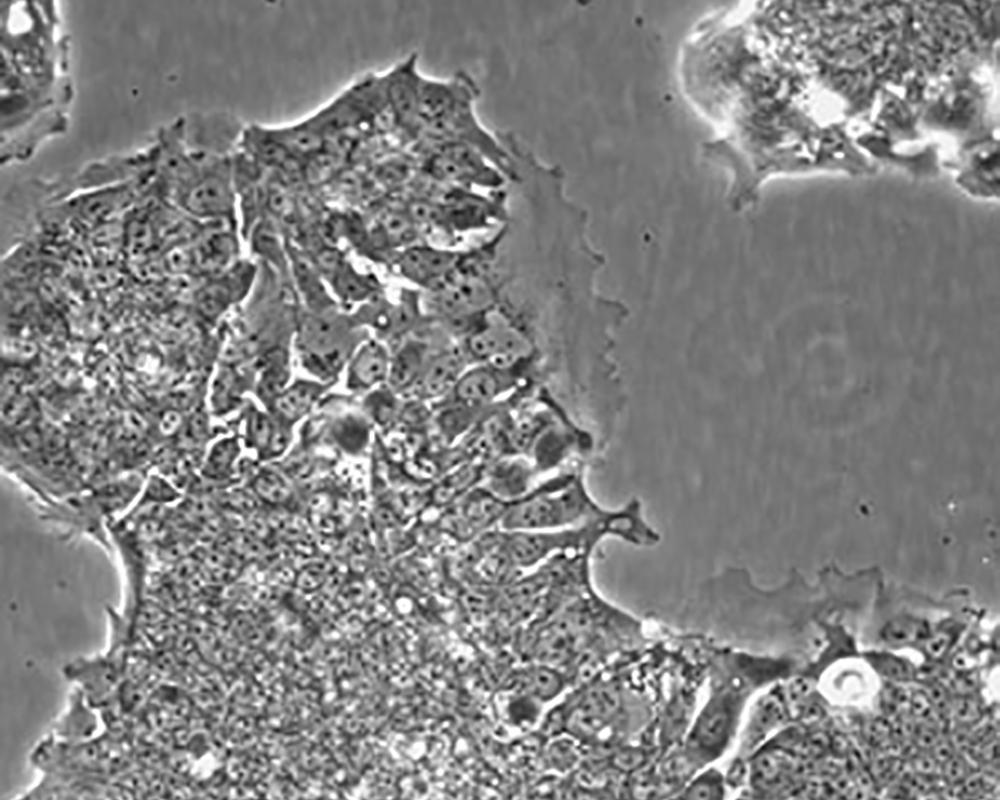

中文名稱 人結腸腺癌肺轉(zhuǎn)移細胞

組織來源 結腸腺癌;肺轉(zhuǎn)移;男性

生長特性 adherent

形態(tài)特征 epithelial

細胞描述 T84細胞株是從一位72歲男性結腸癌患者的肺轉(zhuǎn)移灶建立的可移植人類癌細胞株。 腫瘤組織皮下接種于BALB/c裸鼠,并連續(xù)進行移植。 [26072] 在裸鼠身上的移植過程中,細胞株始終保持結腸癌的原始組織性狀。 [26072] 在無胸腺小鼠中傳代23代后建立了T84細胞株。 這些細胞單層生長到飽和并在接觸細胞間展現(xiàn)出緊密連接和橋粒。 [1155] 有很多關于多肽類激素和神經(jīng)遞質(zhì)并維持定向電解質(zhì)傳輸?shù)氖荏w。 [1155] 這株細胞展現(xiàn)了接觸細胞中的緊密連接和橋粒。 [1155] 角蛋白免疫過氧化物酶染色陽性。